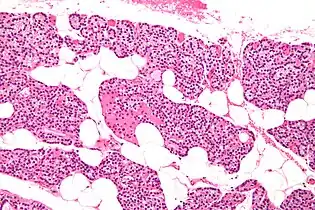

Microanatomy

The parathyroid glands are named for their proximity to the thyroid—and serve a completely different role than the thyroid gland. The parathyroid glands are quite easily recognizable from the thyroid as they have densely packed cells, in contrast with the follicular structure of the thyroid.[6] Two unique types of cells are present in the parathyroid gland:

Intermediate magnification micrograph. H&E stain. The white round structures are fat cells. Adipose tissue comprises 25–40% of normal parathyroid gland tissue.[7]

Intermediate magnification micrograph. H&E stain. The white round structures are fat cells. Adipose tissue comprises 25–40% of normal parathyroid gland tissue.[7] High magnification micrograph. H&E stain. The small, dark cells are chief cells, which are responsible for secreting parathyroid hormone. The cells with orange/pink staining cytoplasm are oxyphil cells